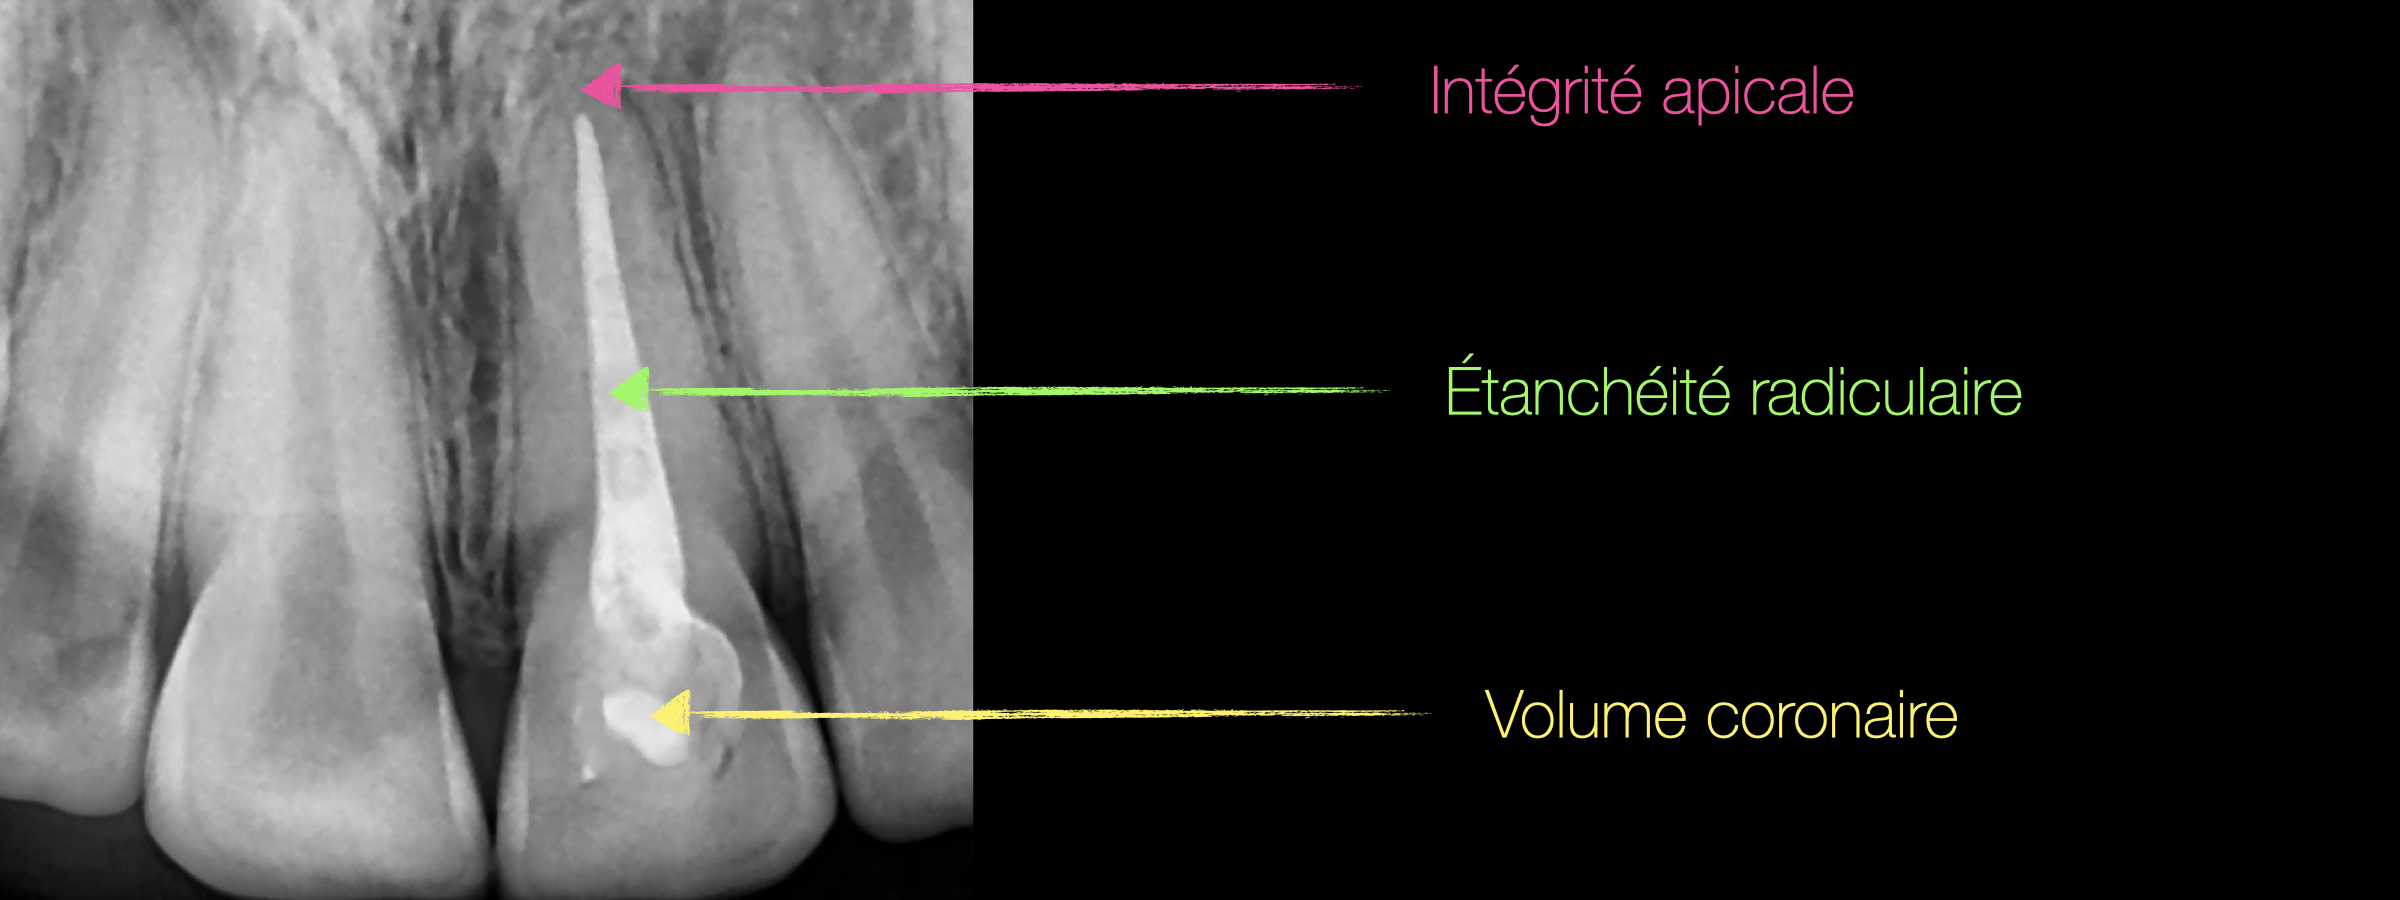

La dyschromie d’une dent dépulpée est essentiellement causée par 3 facteurs :

Un éclaircissement interne d’une dent dyschromiée peut s’envisager si :

- le traitement endodontique est étanche,

Fig. 04 : la radiographie de la 21 montre un délabrement modéré, une obturation canalaire qui semble de bonne qualité et l’absence de pathologie péri apicale.

L’indication d’un éclaircissement interne est donc posée.

Cette dent semble donc conserver une résistance mécanique suffisante pour ne pas nécessiter un recouvrement périphérique mais la vue palatine montre une dégradation du joint composite/dent expliquant certainement une infiltration coronaire.